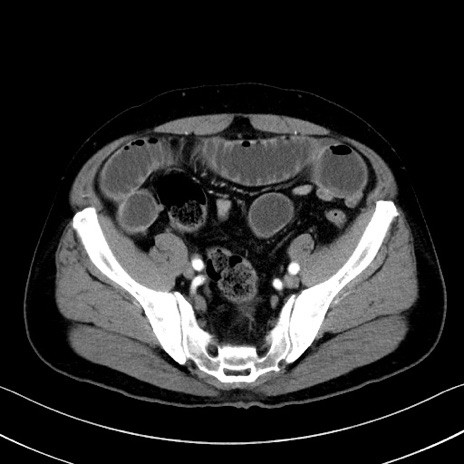

症例35(横断像)

【症例】70歳代 男性

【主訴】腹部膨満、嘔吐

【現病歴】昨日より腹部膨満感出現。本日増悪し、仙痛出現。嘔吐あり、受診。

【既往歴】糖尿病、胆摘後

【身体所見】BP 149/80mmHg、HR 74/min、BT 35.9℃、腹部:膨満、軟、圧痛なし。腸雑音減弱あり。上腹部正中切開瘢痕あり。

【データ】WBC 13500、CRP 1.72